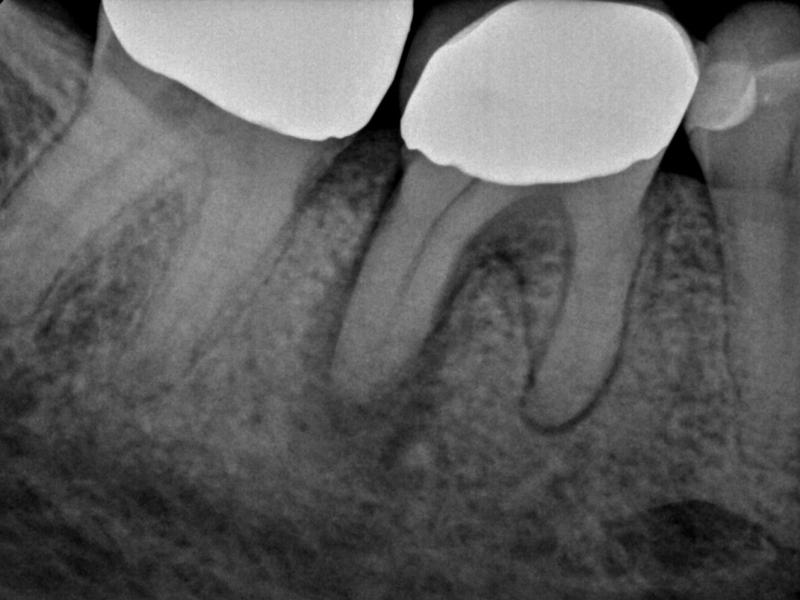

Pre-Op